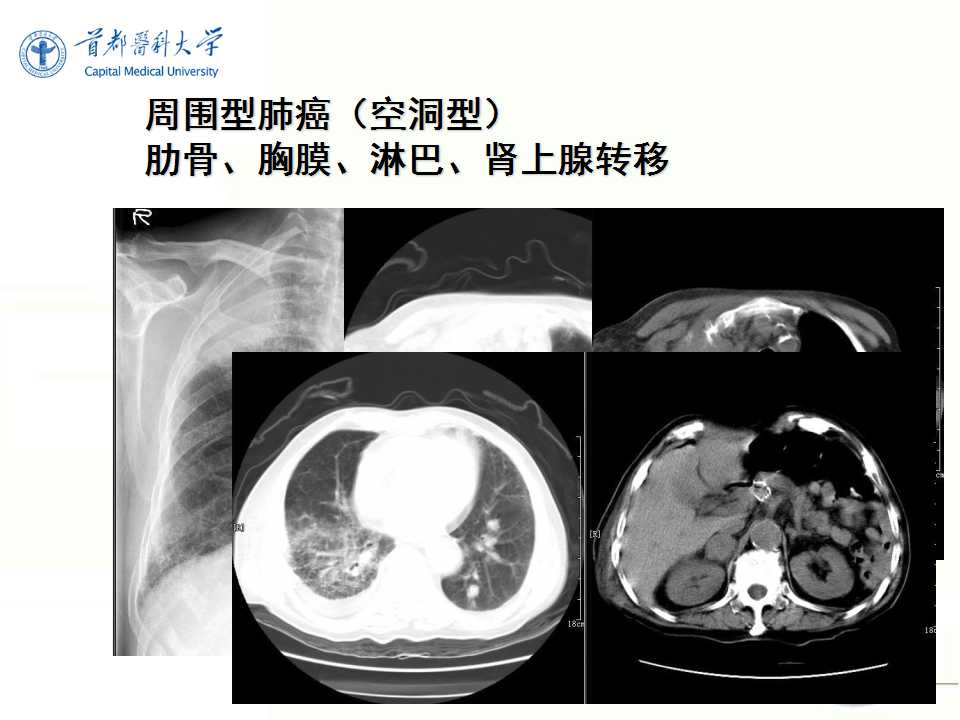

肺癌的影像学检查